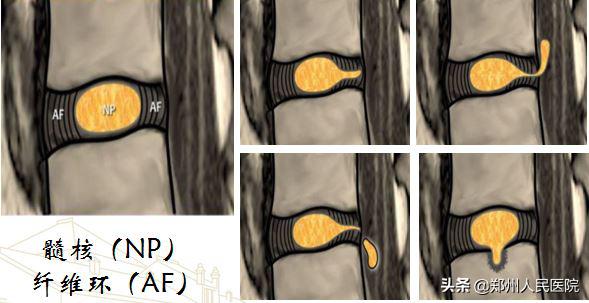

腰椎间盘突出症的类型

如图所示将腰椎间盘突出分为膨出、突出、脱出及许莫氏结节;

又根据突出的位置分为中央型、旁侧型、极外侧型;